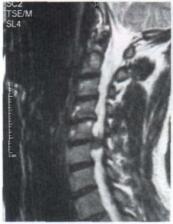

tmpA102-2.jpg

Auch große Bandscheibenvorfälle können erfolgreich mit dieser Methode therapiert werden. Hier handelt es sich um einen gedeckten großen Bandscheibenaustritt zwischen dem 5. und 6. Halswirbel. Nach sechs Wochen war die Patientin bei der Kontrolluntersuchung von ihren heftigen Arm- und Kopfschmerzen befreit.